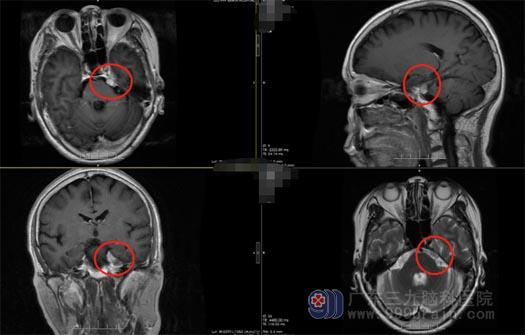

▲术前

▲术后